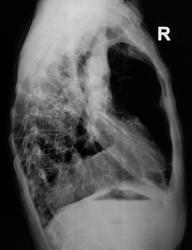

По рентгенограммам фиброторакс как бы неполный, однако, на представленных томограммах правый главный бронх в виде культи, но нечётко видимой. И металл. зажимы в срезы не попали. Там точно всё удалено?

Левое лёгкое с патологией и в нижней доле и в верхней.

Неоднозначно всё

Согласно документам - пульмонэктомия.

Ну пульмонэктомия-значит пульмон эктомия , ничего нового.Только надо иметь ввиду грубое смещение органов средостения и медиастинальная грыжа.

С медиастинальными грыжами понятно. А что ещё светится на месте удалённого лёгкого? При фибротораксе такого не может быть. Когда была операция? И клиники хоть ложку надо.